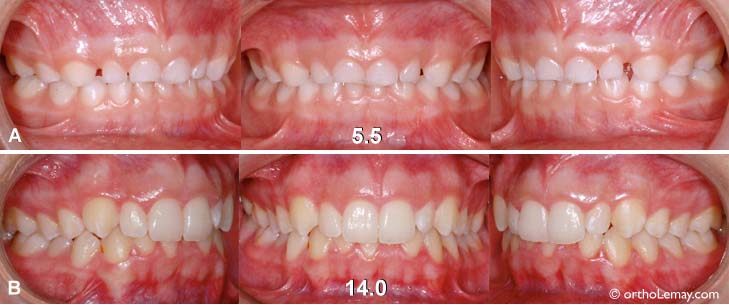

5ans-14ans

Exemple malocclusion malocclusion ce type classe 2 avec surplomb vertical (overbite) excessif (A) à l’âge de 5 ans en dentition temporaire. (B) À l’âge de 14 ans, les dents permanentes ont remplacé les dents de lait (temporaires) mais la même malocclusion persiste malgré la croissance et il existe les mêmes indications pour faire des corrections orthodontiques.